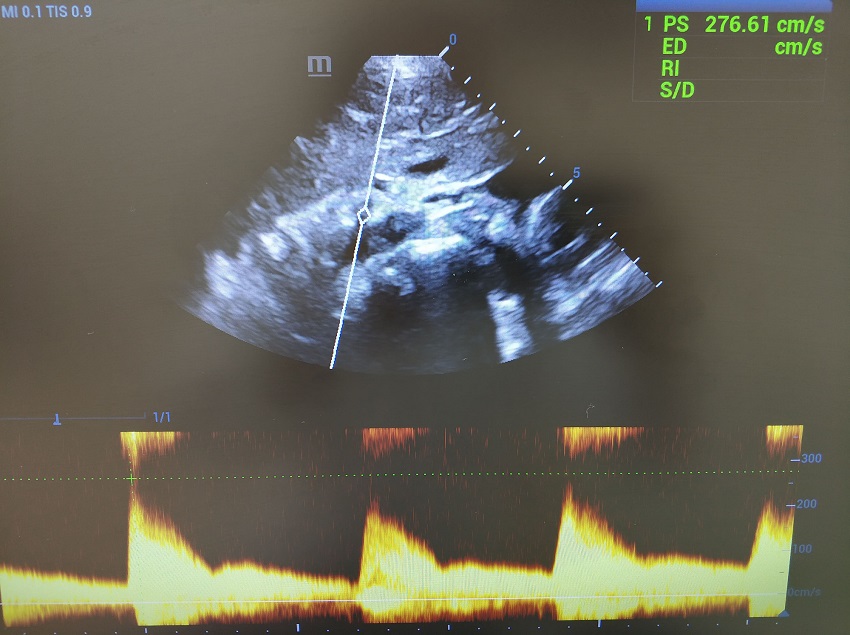

Повторяем маневр, контрольный объем скользит в чревный ствол. Прибор переходит на визг, ручка Scale вправо - увеличиваем шкалу и пульсация затихает. Калипер поднимается на вершину систолического пика, PSV 276 см/сек. Максимум ли? Переходим в режим постоянно волнового CW-допплера, фокус в зону истока чревного ствола. Да, максимум.